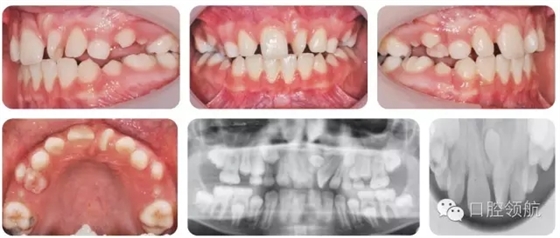

10歲的男性患者,由全科牙醫(yī)轉(zhuǎn)診。該患者健康情況良好,主訴是上前牙不美觀(圖2.16)。

圖2.16

● 混合牙列,III類切牙關(guān)系,前牙覆減小但未出現(xiàn)開牙合。

● 雙側(cè)磨牙1/2牙尖II類關(guān)系。

● 上中線左偏。

● UL1近中腭側(cè)旋轉(zhuǎn)。